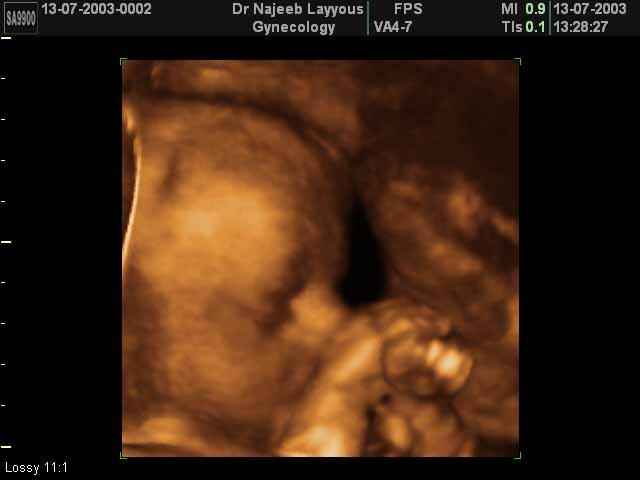

- 3D Fetal Profile Ultrasound Scan Photos

3D Fetal Profile Ultrasound Scan Photos | Dr N Layyous